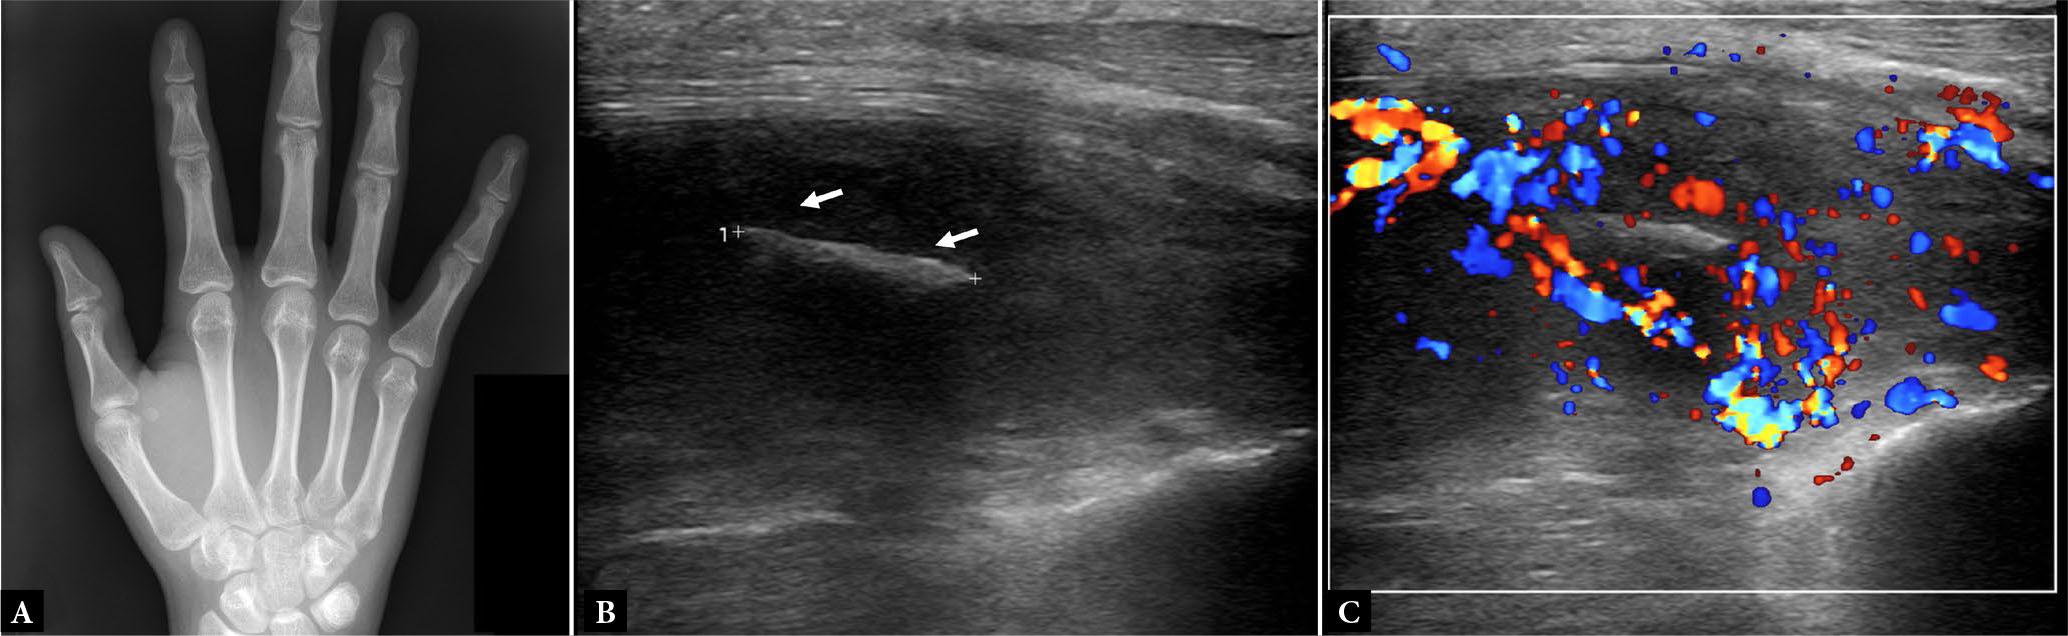

Fig. 1.